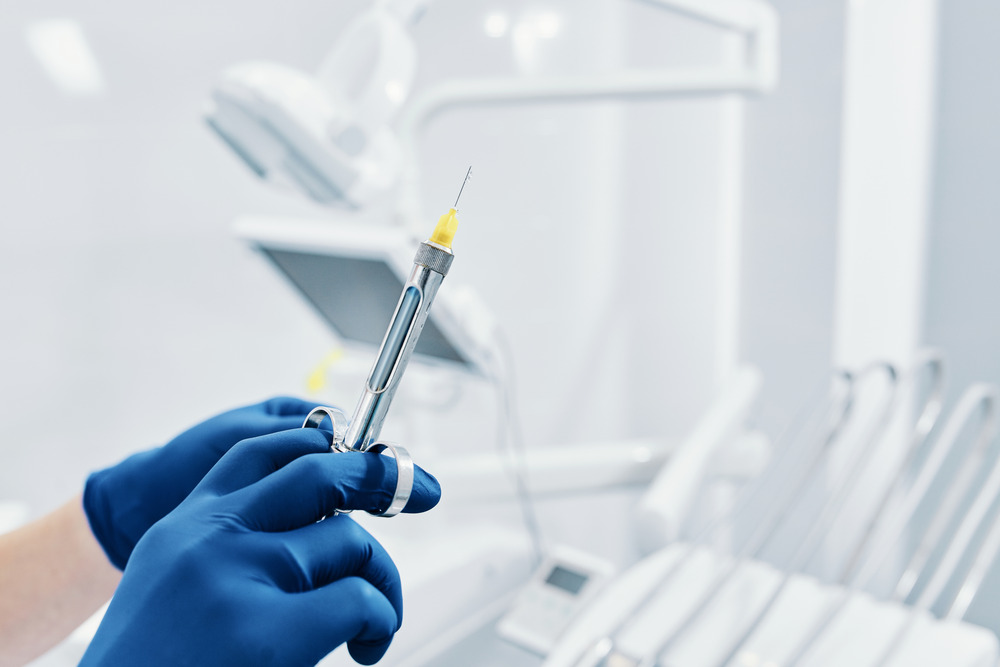

The dental crown procedure typically requires two visits to the dentist. During the first visit, the dentist will numb the area around the tooth and shape the tooth to prepare it for the crown. An impression of the tooth will be taken and sent to a dental lab to create the custom crown. A temporary crown will be placed over the prepared tooth to protect it until the permanent crown is ready.